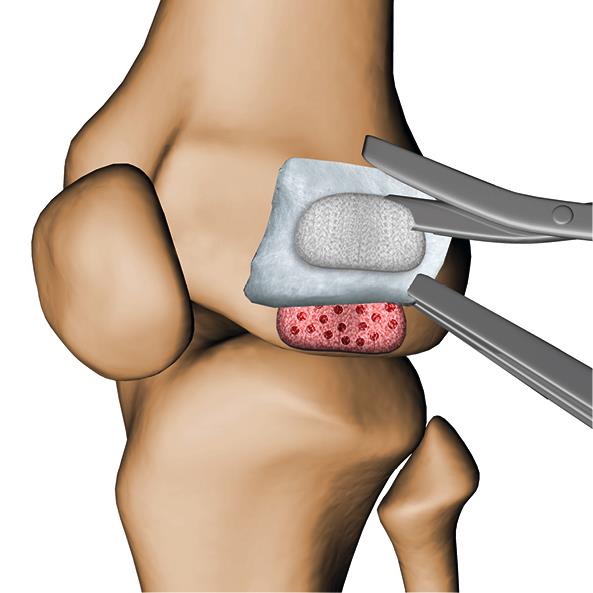

Hier kann eine Bioprothese bestehend aus einer dreidimensionale Matrix und purer Hyaluronsäure zur Behandlung chondraler und osteochondraler Läsionen des Grades III–IV zur Anwendung kommen (Einblendung Bild Bioprothese) Die Bioprothese macht sich das Selbstheilungspotential des Körpers zunutze und ermöglicht in einem unkomplizierten, minimal-invasiven chirurgischen Eingriff die Regeneration von Knorpel-/Knochengewebe. Körpereigene Knorpel- und Stammzellen wandern nach kurzer Zeit eigenständig in die Matrix der Bioprothese ein und bauen das Knorpelgewebe wieder auf. Als körpereigener Bestandteil wird diese Matrix mit der Zeit vollständig vom Körper resorbiert.

Der Einsatz einer Bioprothese baut auf der Mikrofrakturierung, einer etablierten Therapie, auf. Bei der Mikrofrakturierung wird der Defekt repariert, wohingegen die Bioprothese in Kombination mit Mikrofrakturierung einen Schritt weiter geht – die Regeneration des Knorpel-/Knochengewebes wird unterstützt. Die Matrix bietet den knorpelregenerierenden Stammzellen optimale Bedingungen für die Knorpelbildung (die sog. Chondrogenese), weil die nach und nach freiwerdende Hyaluronsäure die biologische Umgebung für Zellen optimiert. Der entstehende Knorpel ist von wesentlich besserer Qualität als nach Mikrofrakturierung und kommt dem ursprünglichen Knorpel nahe.